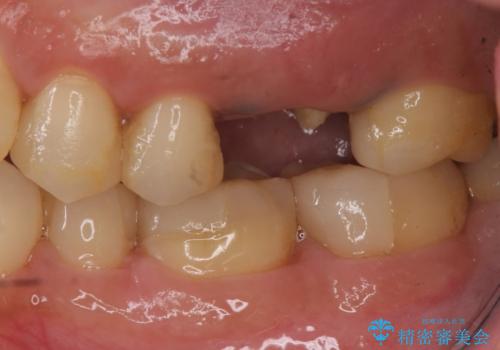

- 検査の結果、長くもたせることが困難な歯が確認された患者様です。

抜歯を行い、周囲の骨を増やしつつインプラントを埋入することとなりました。

手前の歯の虫歯もセラミックインレーで精度よく治療を行いました。